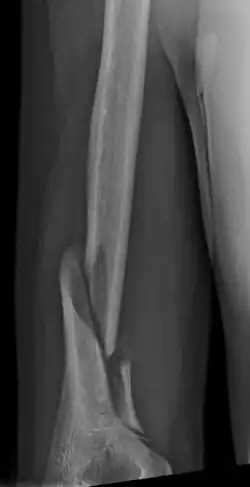

Holstein–Lewis fracture at 5 weeks post fracture

A Holstein–Lewis fracture is a fracture of the distal third of the humerus resulting in entrapment of the radial nerve.